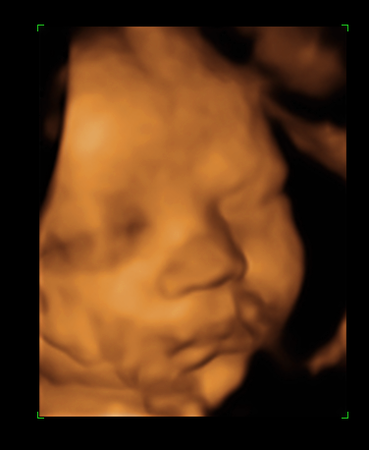

Наконец мы сделали это!!!Сегодня ходили на УЗИ.Малыш умничка, перевернулся головкой вниз)))А ещё был(а) безумно серьёзен и временами немного недоволен))))И мы сделали наши первые фотографии)))Моей радости просто нет предела!!!

недовольно трём глазки и морщимся))))